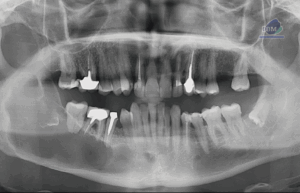

Paciente femenino de 87 años de edad, es referido al Instituto de Diagnóstico Maxilofacial – IDM para evaluación general.En la radiografía panorámica (Figura 1), se